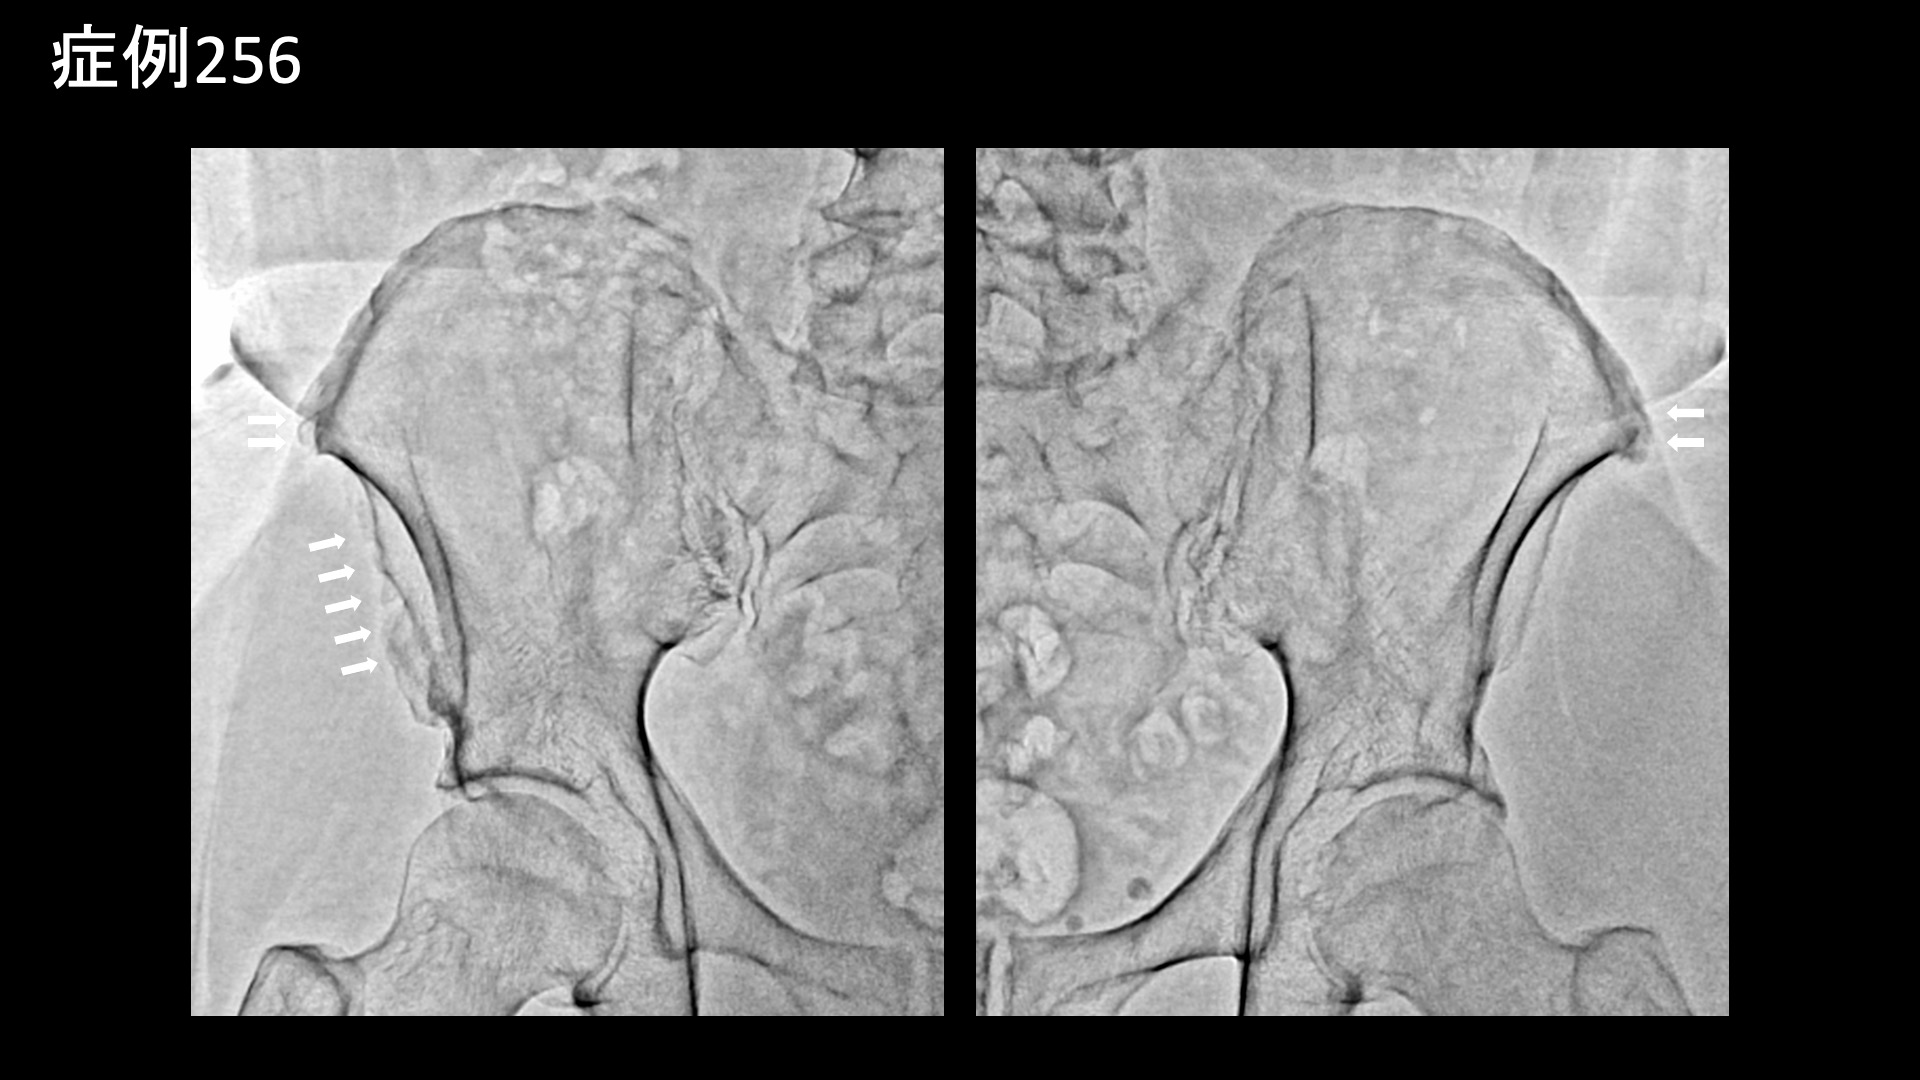

腰:椎間関節炎など 【60代:男性】15年前からの慢性腰痛が急激に悪化して夜も寝られず・・ヘルニアは悪さをしていないなら原因は?(筋・筋膜性疼痛症候群、仙腸関節障害、腰椎椎間板ヘルニア) 2025.12.23 鴨井院長による動画解説 受診までの経過 15年前から慢性的に腰痛がありました。1年前にひどい痛みと脱力に襲われ、MRI検査を受けたところ、腰椎椎間板ヘルニアと診断されました。手術も検討していましたが、自然軽快し、再び歩けるようになりました。しかしながら、右側の腰痛は軽快したものの、左側の強い腰痛が残っていました。ヘルニアで強く圧迫されていたのは右側の神経であったため、整形外科では首を傾げられました。じっとしていると増悪し、長時間の立位でも増悪しました。そのため、夜痛みで寝られないことが多く、起床後も11時くらいになってようやく動けるようになる状態でした。 *50年前に腸骨骨折の既往あり 診察時の所見 MRI検査を確認すると、やはりヘルニアで圧迫を受けているのは右側であり、ヘルニア所見と症状は合致しませんでした。腰の可動域をチェックすると。すべてに動作において中等度の制限がありました。股関節の内外旋動作では可動域は保たれているものの、動きに抵抗があり比較的高度の硬さがありました。触診では、第2―4腰椎レベルでは左腰部の筋肉部において有意に圧痛が認められました。レントゲンでは、左上前腸骨棘を中心に腸骨に骨表層不整像や骨硬化像が見られており、同部位に付着する腸骨筋、縫工筋、大腿筋膜張筋が関与する筋・筋膜性の障害が示唆されました。いずれも股関節の動きに関与する筋肉です。腸骨にはほかに腸腰筋や臀筋が関与し、いずれも腰臀部痛の原因として重要です。こうした腸骨の変化や、筋硬直、その他の特徴的な身体所見から総合的に判断して、筋・筋膜性疼痛症候群を主体として、仙腸関節障害も合併している状態と判断しました。骨盤の不安定性が一因ですので、腸骨骨折の既往とも関係があるかもしれません。以上より治療適応と判断し、モヤモヤ血管(病的新生血管)に対する運動器カテーテル治療(微細動脈塞栓術)を受けていただきました。 治療の所見 第2腰動脈~第4腰動脈の筋肉枝を選択的に治療し、さらに、腰痛の主要責任血管の一つである腸腰動脈や外側仙骨動脈、臀筋群に関与する上殿動脈、下殿動脈、股関節の動きにも関わる閉鎖動脈やその他の筋肉枝など複数個所の治療を広範囲に行いました。 治療後の経過 治療後2週間、まだ大きな変化はないものの、痛みが少しましになったほか、寝られる日が多くなってきました(以前は痛みで寝られないことが多かった)。治療後1ヶ月半、時々痛むことはあるものの、だいぶ良くなってきました。痛みで寝られないということは無くなりました。『本当に寝られなくて辛かったので嬉しい、何十歳か若返ったように思う』と大変喜ばれました。まだ左腰部に1か所だけ、塊のように感じる部分が残っているものの、それもだいぶ柔らかくなりました。治療後3ヶ月、塊の部分はやはり一定の違和感があるものの、痛みは感じなくなりました。全体的には疲れると疼くように痛むことがあるものの、元の7割程度の痛みは解消されました(3/10程度に改善)。夜寝られないほどの腰痛というのはかなり重症度が高いわけですが、これほどの状態であっても、MRIで原因がわからないことは珍しくありません。丹念に診察をして原因を見つけ出し、治療を行うのが痛み治療専門医師の腕の見せ所ですが、良い結果が得られて本当に良かったです。残存症状については追加カテーテル治療が有効ですが、生活習慣の改善や運動療法を地道に行っていくことでさらなる緩和が期待できます。引き続きしっかりとサポートしていきたいと思います。 本症例では、とにかく体の硬さや筋硬直が根底にありました。こうした状態では、腰痛はほぼ必発です。骨格のほか、運動不足や、過剰なトレーニング、急激な体重変動、加齢などが原因です。懸念のある方は、発症予防、再発予防のために硬さの解消に取り組んでください。原因により対処方法は異なりますが、日常的に軽めの運動を取り入れることはいずれの場合も有効です。 筋・筋膜性疼痛症候群の詳細はこちら 【70代:男性】頭痛、こめかみ・眉上の痛み、耳鳴り~頭部顔面の帯状疱疹後遺症に対するモヤモヤ血管治療(帯状疱疹後遺症) 前の記事 【50代:女性】8年前からの両膝・両足首の痛みに加えて踵まで痛み平地歩行もままならず・・進行性の変形性膝関節症および足関節症、足底筋膜炎の合併例に対して2回の運動器カテーテル治療を行った症例(変形性膝関節症、変形性足関節症、足底筋膜炎、肥満) 次の記事